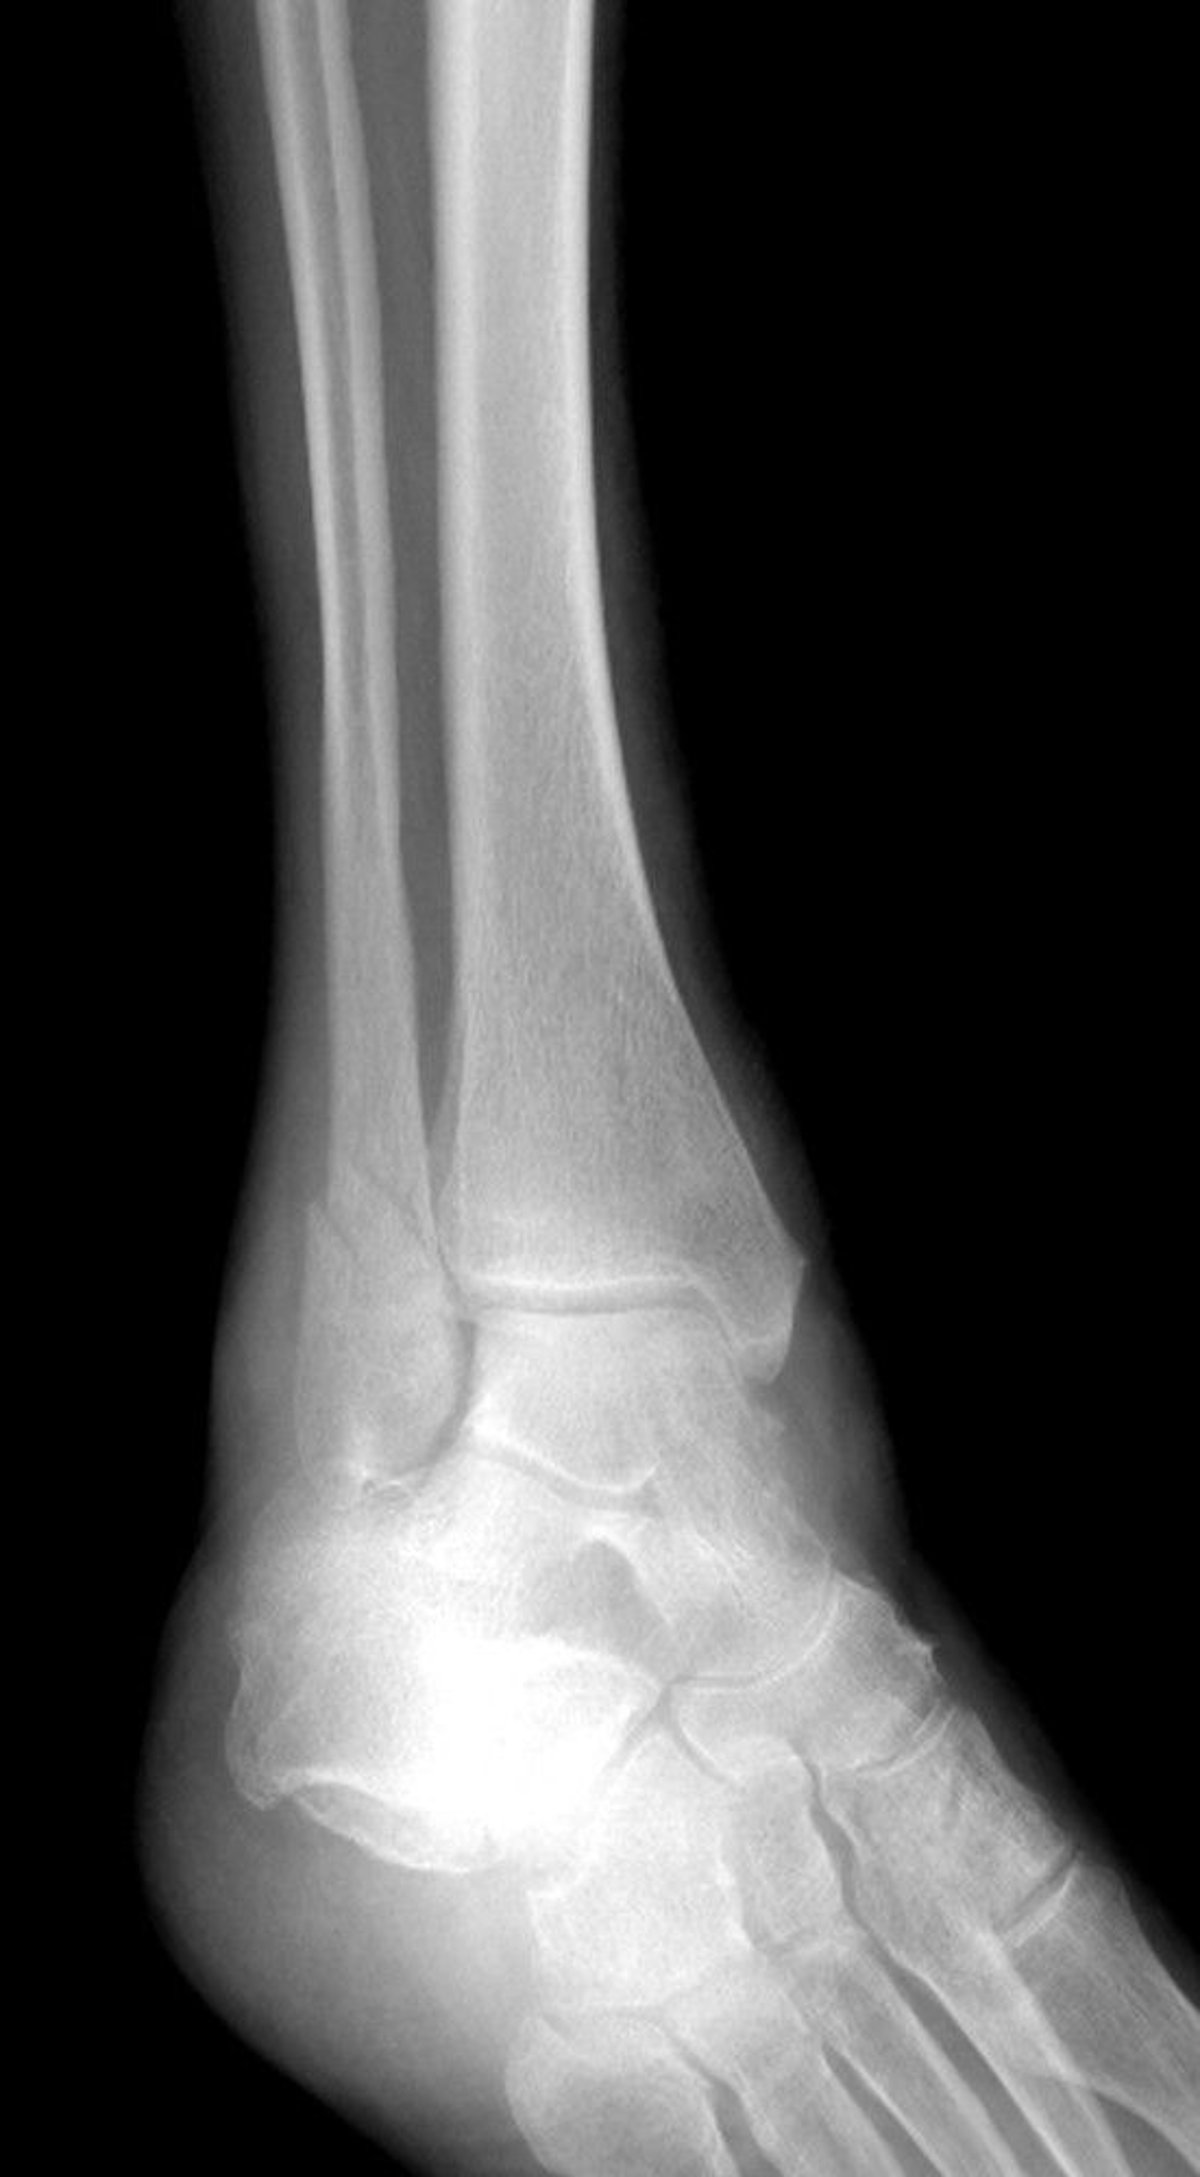

Fracture of Lateral Malleolus

This ankle fracture affects the lateral malleolus but spares the medial malleolus.